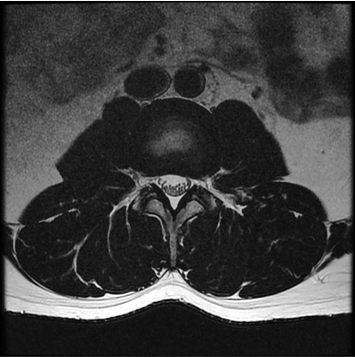

3:00 minIAI (Innovative AI)

384 x 256 (2 NEX)

1:29 minscan time reduced up to 50%

IAI는 AI Deep learning을 통해 기존 장비의 촬영 프로토콜을 최적화합니다.

기존 프로토콜 대비 촬영 시간을 50% 단축시키며, 이미지 퀄리티는 증가합니다.